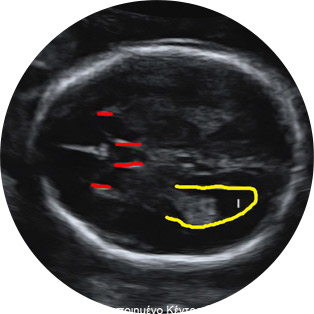

Οι βασικές τομές που λαμβάνονται είναι η τομή των 4 κοιλοτήτων της καρδιάς, όπου ανακαλύπτεται το 60% των βλαβών της, η τομή εξόδου της αορτής και της πνευμονικής αρτηρίας, καθώς και η τομή των 3 αγγείων όπου γίνεται ενδελεχής έλεγχος των μεγάλων αγγείων και των συνδέσεων μεταξύ τους. Σε τυχόν υπόνοιες βλαβών, λαμβάνονται επιπλέον τομές ή ζητείται ειδικός υπερηχο-εμβρυο-καρδιολογικός έλεγχος του εμβρύου.